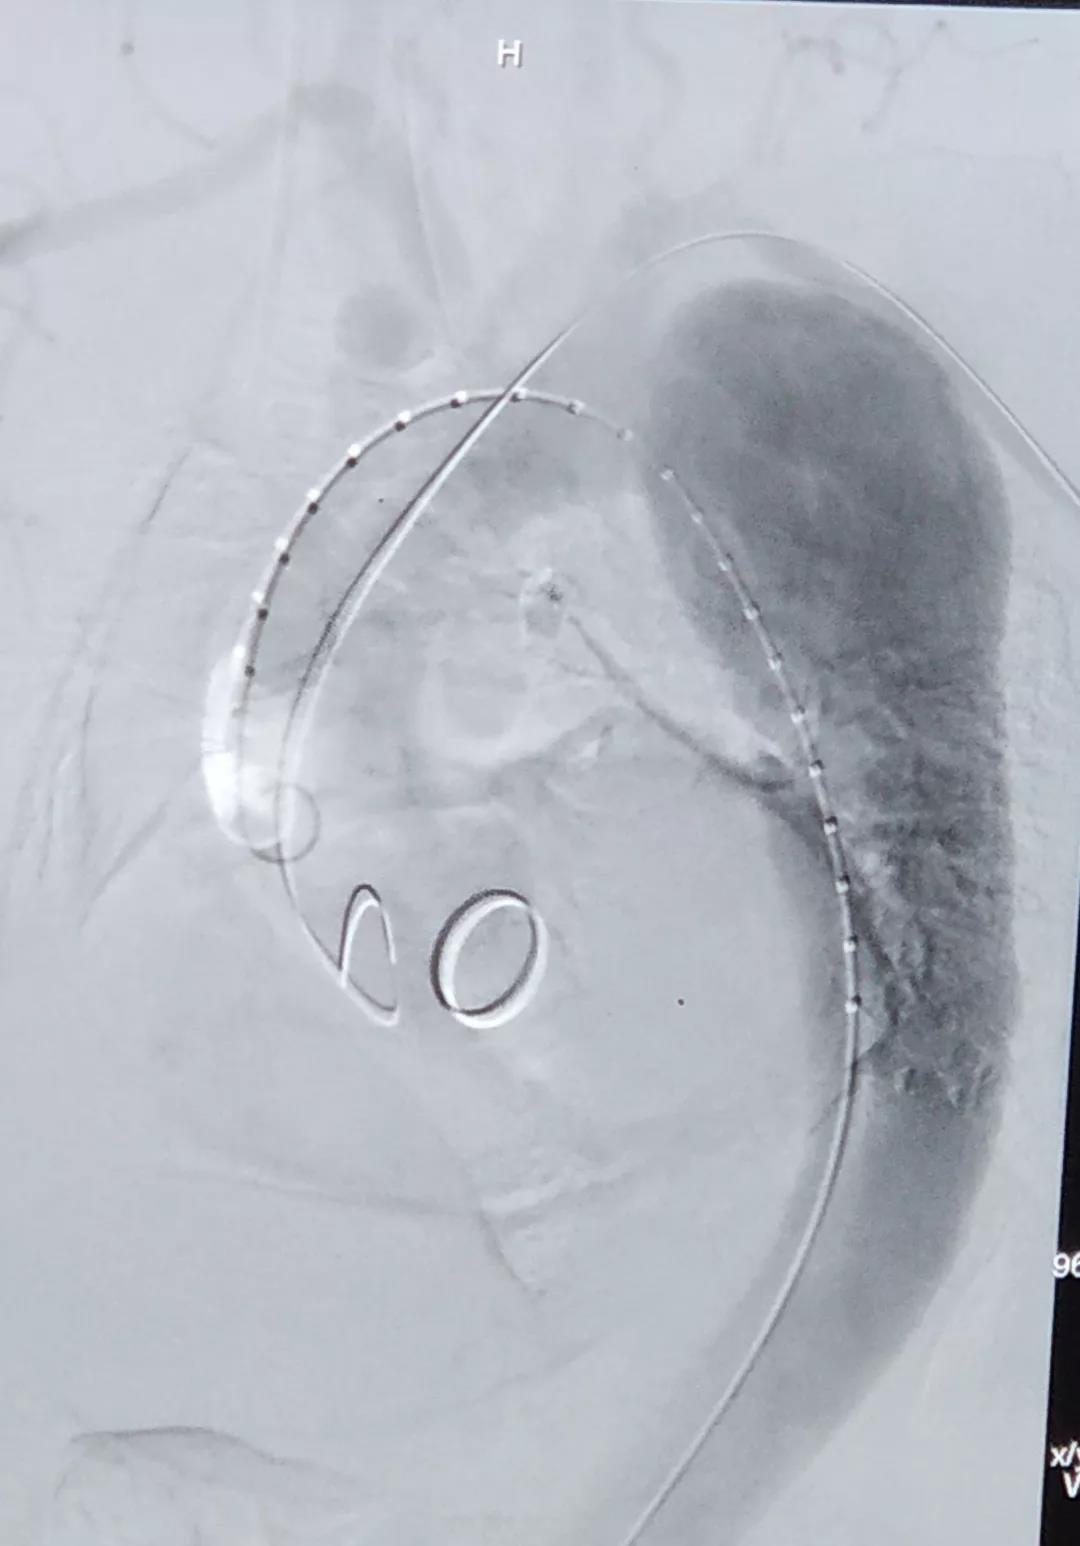

术中通过DSA造影显示:主动脉夹层破口位于左锁骨下动脉近端,真腔压闭。舒畅教授通过左锁骨下动脉预置Longuette™裙边支架,释放 Ankura™ Pro主动脉主体覆膜支架,封堵破口后通过裙边支架显影点准确定位,释放裙边支架,凭借着舒畅教授精湛的手术操作和器械的优异性能,手术过程非常顺利,胸主动脉支架释放良好,患者的主动脉夹层破口封闭良好,左锁骨下动脉释放的裙边支架血流通畅,没有内漏发生。由于患者远端真腔较小,为了保证远端的血流,植入了一个cuff支架,造影显示远端真腔打开良好。

(图:术前造影)